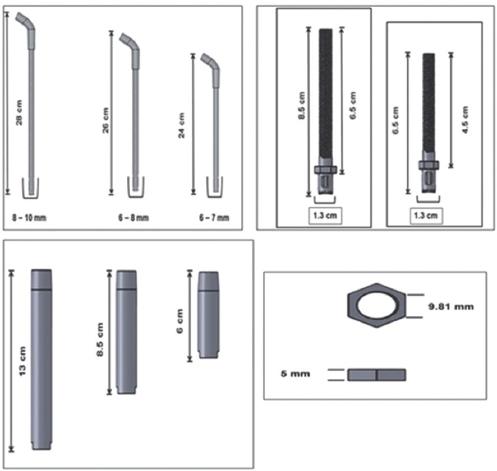

El material utilizado en la prótesis es Ti-6Al-4V, y en la cabeza de la prótesis se combina con polietileno de alta densidad. El peso aproximado de la prótesis humeral oscila entre 350 y 550 g (Fig. 1).

Figura 1 Componentes de la endoprótesis tumoral no convencional de hombro y su colocación. A: vástago. B: corona con cuerda. C: camisa o espaciador modular. D: tuerca. E: cabeza humeral. Diseño del Dr. Genaro Rico Martínez, Instituto Nacional de Rehabilitación "Luis Guillermo Ibarra Ibarra".

El sistema de prótesis no convencional RIMAGMR para el húmero proximal cuenta con un cuerpo fijo de 23-26 cm como vástago principal, con orificios en la cara externa de la curva proximal para la inserción musculotendinosa.

La región distal del vástago tiene dos orificios para el bloqueo con pernos de 3.175 mm (1/8 pulg) de diámetro de separación, un espaciador modular expandible mediante tornillo de ajuste (hasta 5 cm) con una corona para rodear el hueso en el sitio de la osteotomía y con ventanas para dar más estabilidad entre el binomio hueso-implante, donde posteriormente se espera el crecimiento del hueso a través de la ventana.

El set contará con tres vástagos, con un diámetro de 6-10 mm y una longitud de 24 cm para húmeros chicos, 26 cm para húmeros medianos y 28 cm para húmeros grandes; tres espaciadores modulares con longitudes para húmeros chicos de 6 cm, para húmeros medianos de 8.5 cm y para húmeros grandes de 13 cm; y dos coronas, con cuerda de 6.5 y 8.5 cm de longitud, y un diámetro de las coronas de 1.3 cm. También se contará con una tuerca con medida de 5 mm. El set de endoprótesis de húmero constará de 14 piezas con diferentes dimensiones (Fig. 5). La prótesis se debe colocar a partir de 4 cm pasando la fosa olecraneana en la parte distal del húmero (codo).